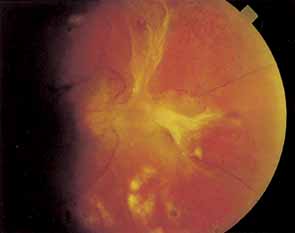

Proliferative vessels usually arise from veins and often begin as a collection of fine vessels. When they arise on or within 1 disc diameter of the optic disc they are referred to as neovascularization of the disc (NVD) (Fig. 9). When they arise further than 1 disc diameter away, they are called neovascularization elsewhere (NVE) (Fig. 10). NVE nearly always grows toward and into zones of retinal capillary nonperfusion, but capillary nonperfusion is nearly always more widespread in eyes with NVD than it is in NVE.12 Interestingly, it is seen more often in patients younger than 40 compared to older patients with diabetes.13

Fig. 9 Advanced neovascularization of the disc.